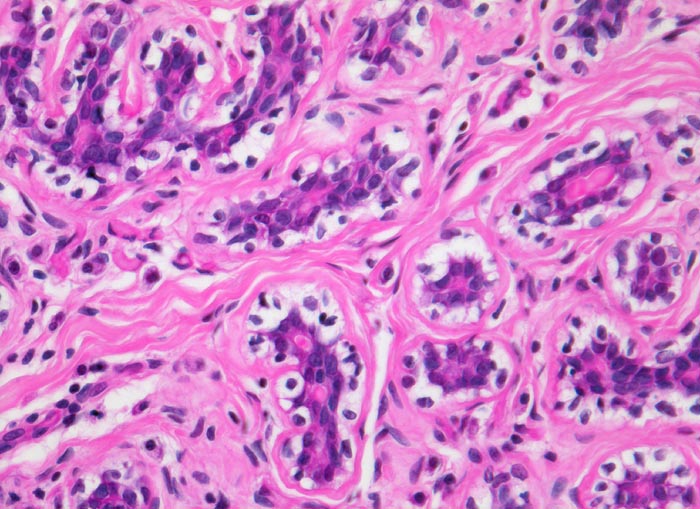

ruhende Mamma: normales Brustdrüsenläppchen

Die Tubuli des Mammaläppchens sind ausgekleidet durch ein einreihiges Epithel. Daran angrenzend die Myoepithelschicht aufsitzend auf einer Basalmembran. Myoepithelzellen mit auffallend balloniertem klarem Zytoplasma. Das Läppchenstroma ist meist etwas lockerer als das interlobuläre Stroma.

Das ruhende Mammaläppchen enthält lediglich Tubuli. Die Mamma lactans besteht aus tubuloalveolären Drüsen.